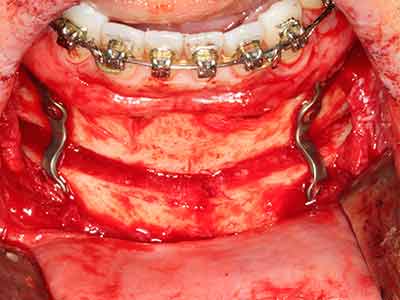

Bone tissue is not simply a mineral structure but also contains a substantial proportion of collagen fibres. This means it not only has good compressive strength but also a degree of flexibility, which can be taken advantage of when performing bone augmentations. In the classical expansion procedure using bone splitting, the atrophied alveolar ridge is split longitudinally and carefully expanded after reaching an adequate osteotomy depth (Fig. 13-16), ideally without substantial removal of the periosteum (Brugnami, Caiazzo et al. 2014, Stricker, Fleiner et al. 2014). Screw and plate systems with increasing expansion distance have proven effective in separating the two bone lamellae while remaining below the fracture threshold. In general, residual bone widths of at least 3–4 mm are required (Chiapasco, Zaniboni et al. 2006) to guarantee adequate flexibility and sufficient bone coverage of the future implants. If necessary, a vertical relief osteotomy on one or both sides can improve flexibility. A combination with additional augmentation techniques, particularly on the buccal side, has been described as an alternative to the classical technique.

The splitting procedure is particularly atraumatic and there is no significant loss of dimension when using piezosaws, and there are no significant differences between implants in split jaws and implants in an alveolar ridge without a bone deficit (Chiapasco, Zaniboni et al. 2006, Danza, Guidi et al. 2009). However, sufficient continuous irrigation is essential, particularly with locally restricted and deep splitting to prevent thermal stress in the apical osteotomy regions.